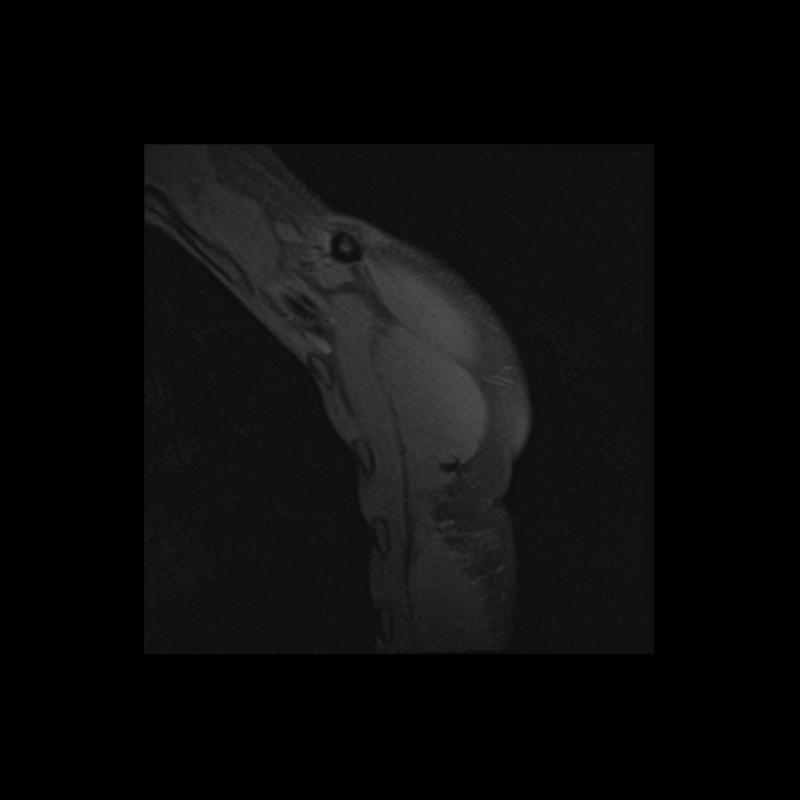

Shoulder MRI Anatomy